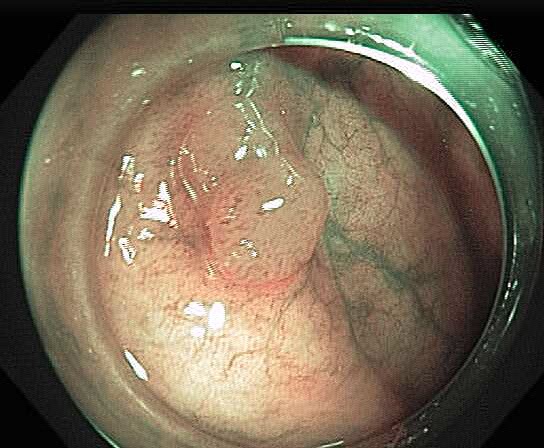

Colonoscopy is the main diagnostic procedure to detect and recognize polyps located on colorectal walls. The accurate detection and correct classification depend on the skills and experience of the endoscopists, however, even for experienced endoscopists, working on conventional colonoscopy for long hours leads to mental and physical fatigue and degraded analysis and diagnosis. Other factors that may affect the classification results include varying illumination conditions, variant texture and appearance, and occlusion. Moreover, different types of polyps are hard to differentiate since they may exhibit a very similar appearance with a subtle difference, as shown in Fig 1. It requires a thorough examination of fine details to distinguish one category form the other. Therefore, an accurate and effective automatic computer-aided system for colonoscopy is required to help endoscopists to detect and classify the type of polyps. This automated recognition mechanism can also be used as a second opinion to determine whether a further biopsy is required for diagnosis, which in turn will greatly reduce the cost of diagnosis. In addition, such an intelligent system can also be used as an educational resource for gastroenterology trainees to reduce the learning curve and cost.

![]() |